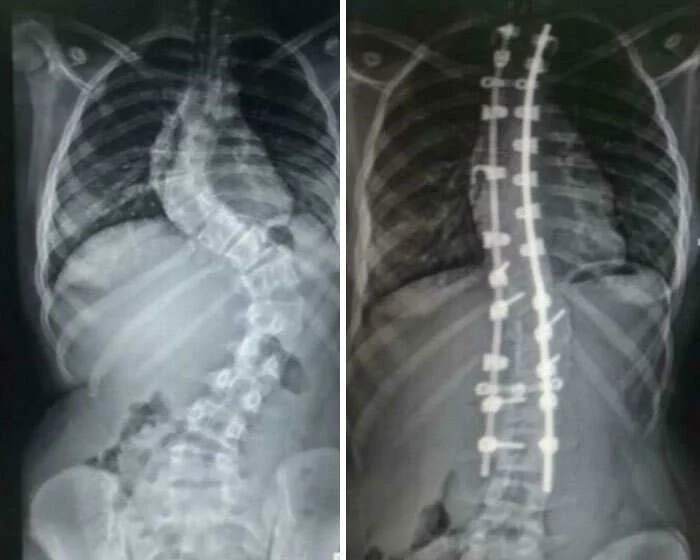

4. Позвоночник до и после спондилодеза